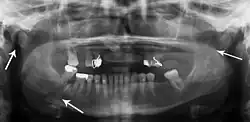

multiple mandible fractures of a patient in the right condyle (extracapsular/neck/not dislocated), right body (vertically unfavourable) and left coronoid process

Panoramic radiography

Panoramic radiographs are tomograms where the mandible is in the focal trough and show a flat image of the mandible. Because the curve of the mandible appears in a 2-dimensional image, fractures are easier to spot leading to an accuracy similar to CT except in the condyle region. In addition, broken, missing or malaligned teeth can often be appreciated on a panoramic image which is frequently lost in plain films. Medial/lateral displacement of the fracture segments and especially the condyle are difficult to gauge so the view is sometimes augmented with plain film radiography or computed tomography for more complex mandible fractures.